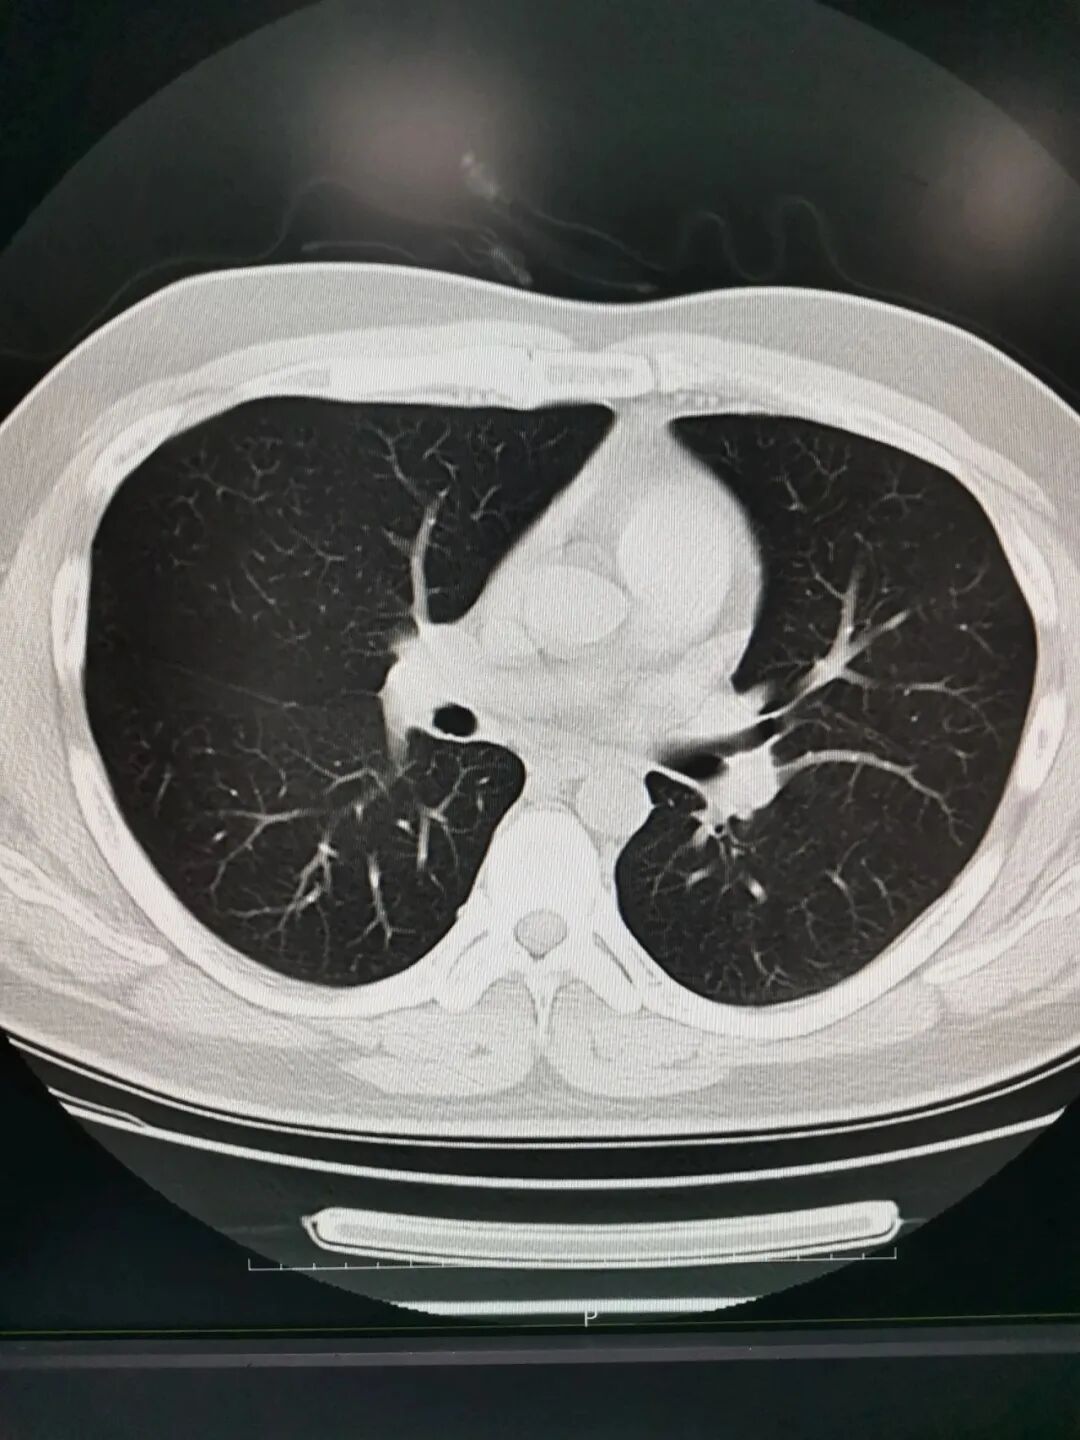

CT 像把面包切片看

CT的检查原理是利用X线分层穿过人体,之后通过电脑计算后二次成像,就像把一块面包切成片来看。优点是可以分层看,经计算后可以显示出更多的组织信息。

CT分辨率高,细节显示好。

3、胸部——粗看X光片,细看CT。

胸部CT检查显示出的结构更清晰,对胸部病变检出敏感性和显示病变的准确性均优于常规X光胸片,特别是对于早期肺癌筛查有决定性意义。但是CT检查的辐射剂量高于X光。核磁共振对于肺部疾病的诊断,应用非常有限。

4、腹部盆腔——一般选择CT,X光和核磁共振根据需要可以选择。

腹腔器官受呼吸影响较大,进而影响到CT、核磁成像,所以检查时需要配合屏气,以提高对肝脏、脾脏、胰腺、肾脏、盆腔脏器的诊断准确率。